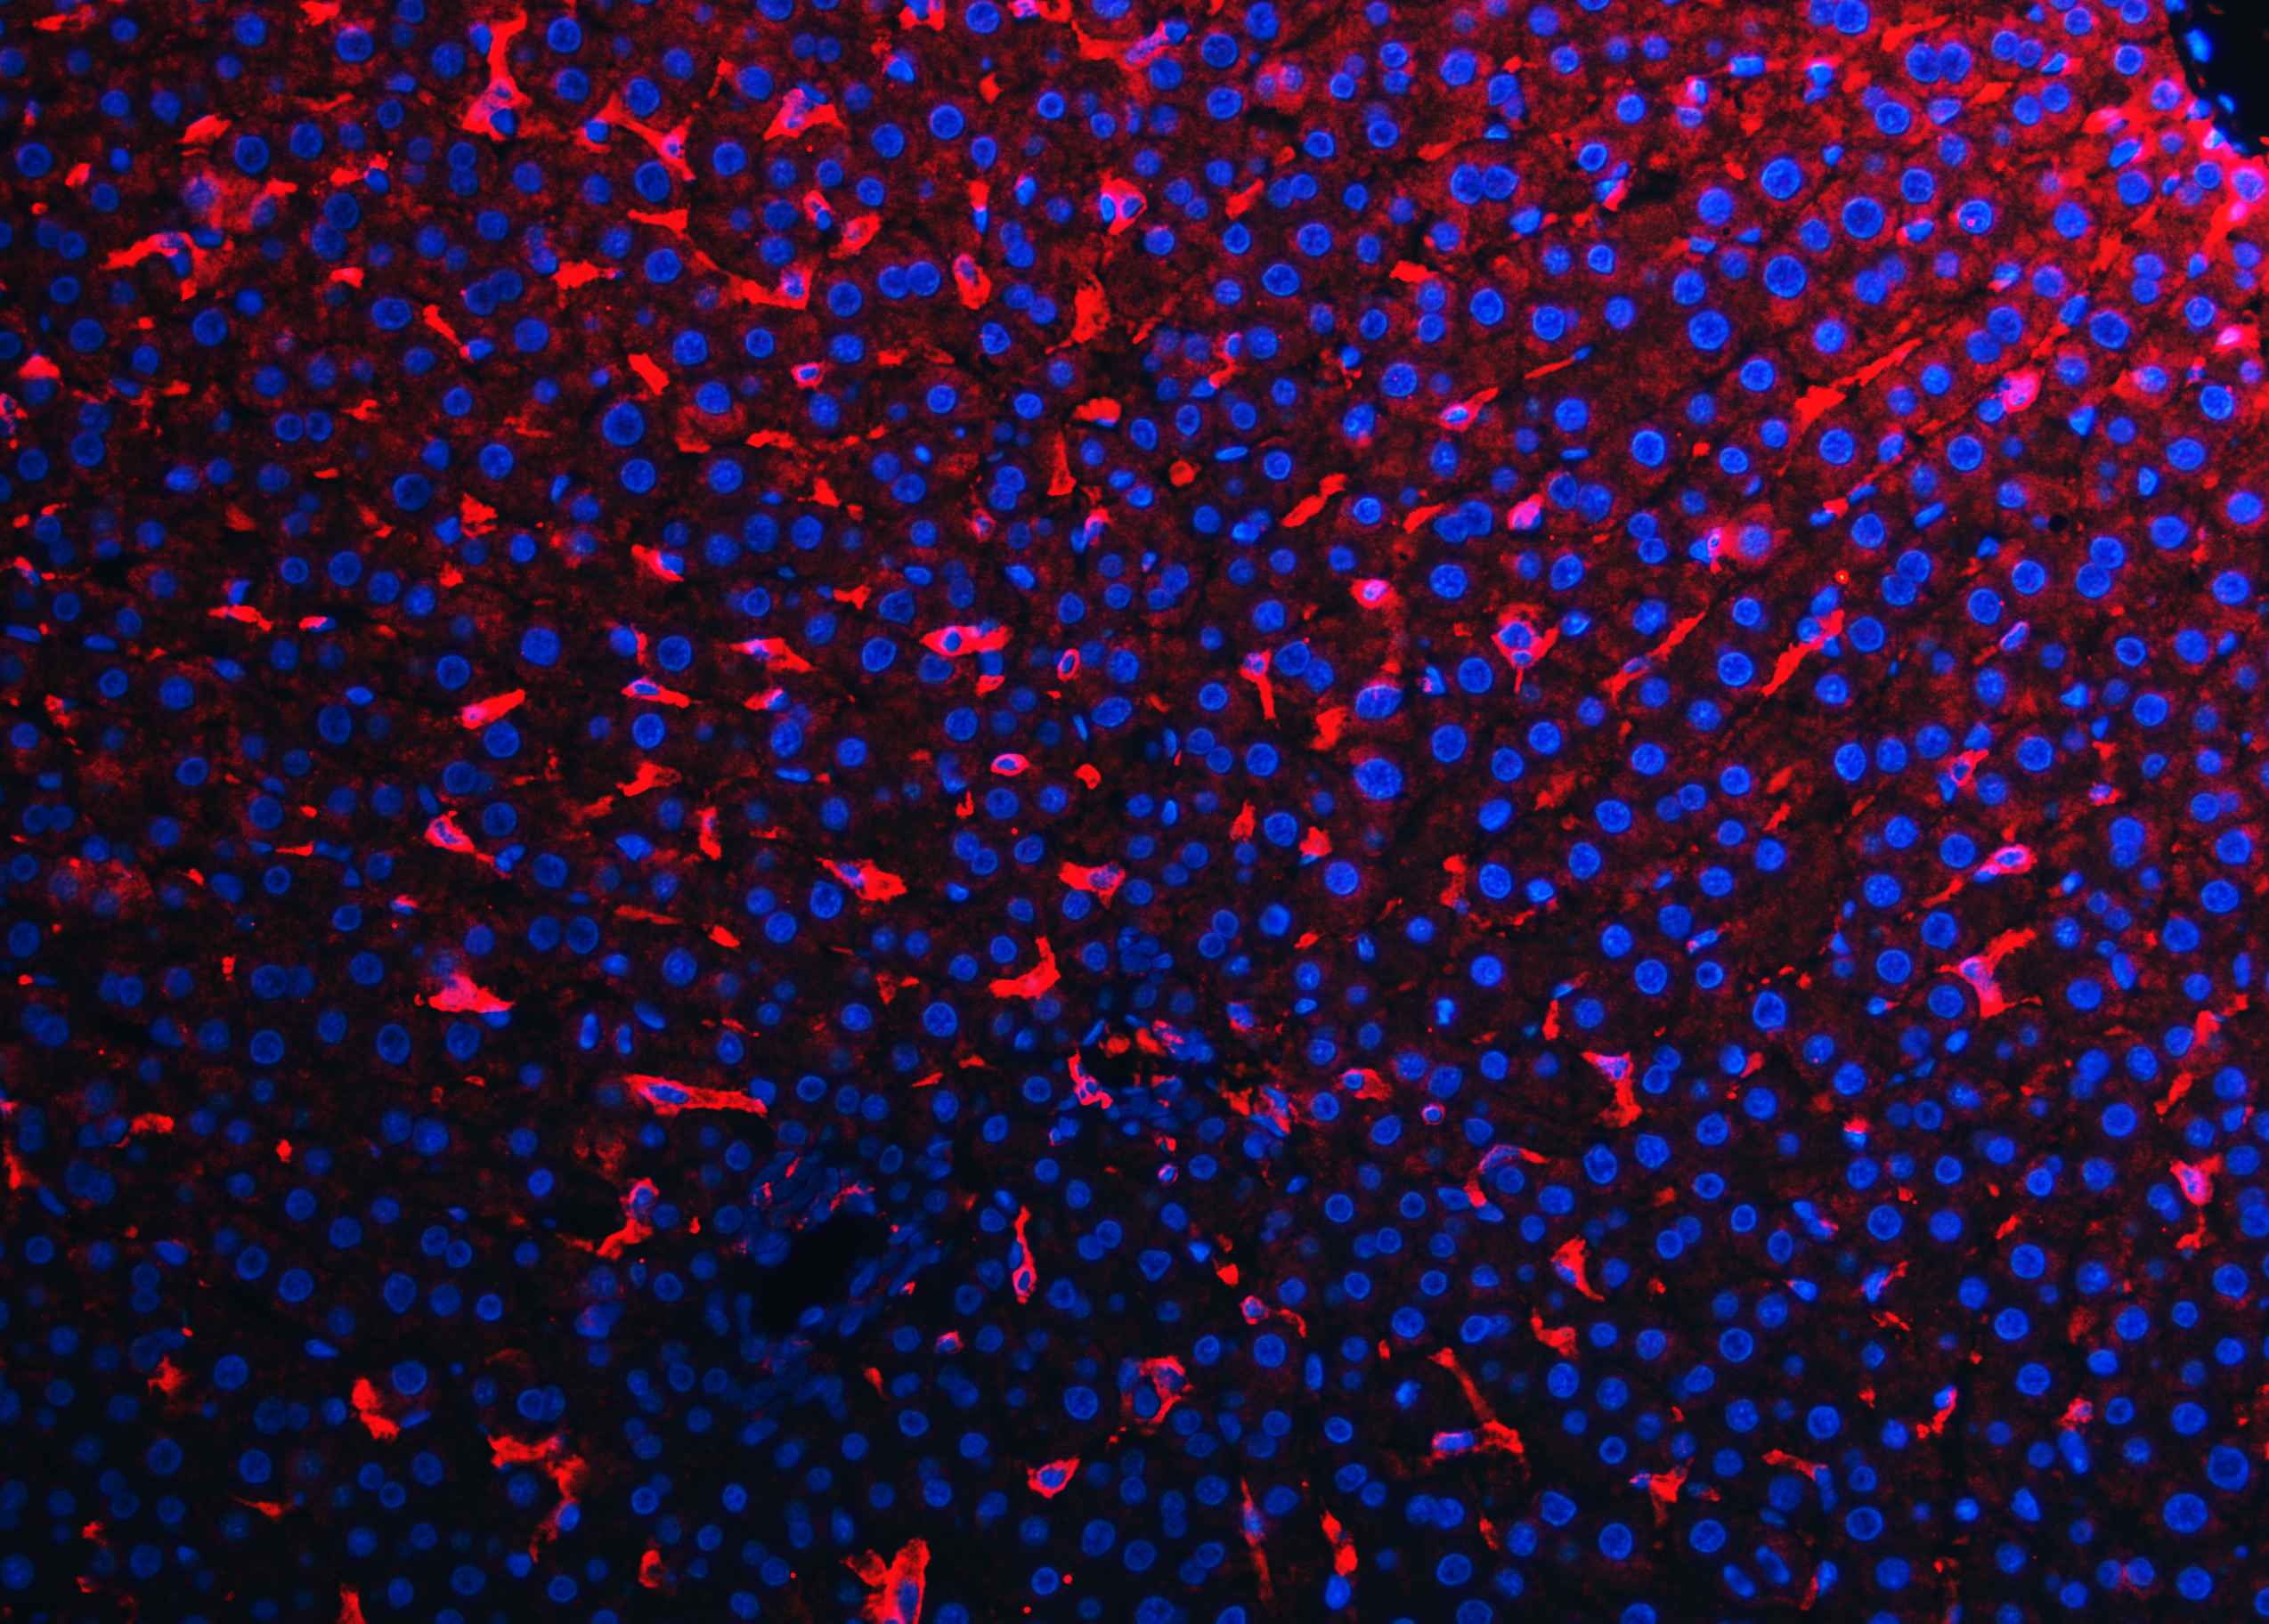

IF analysis of F4/80/Adgre1 using anti-F4/80/Adgre1 antibody (A08751).

F4/80/Adgre1 was detected in a paraffin-embedded section of rat liver tissue. Cy3-conjugated Anti-rabbit IgG Secondary Antibody (red)(Catalog#BA1032) was used as secondary antibody. The section was counterstained with DAPI (Catalog # AR1176) (Blue).